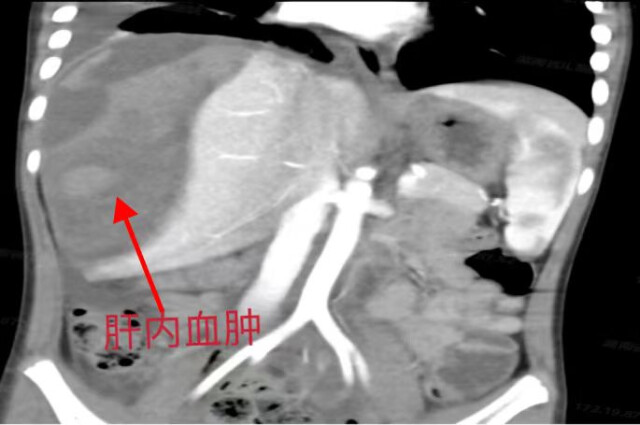

家住娄底的男孩成成(化名)今年6岁,暑假期间与哥哥玩得十分开心,一天下午,成成玩滑板车时与哥哥嬉戏追赶,不慎摔倒,腹部受到严重的冲击撞伤导致肝脏破裂出血,因病情危重从当地医院由救护车紧急送至湖南省儿童医院普外一科接受治疗。成成入院时病情十分危重,肝脏受损面积大,右侧肝脏几乎“破碎”,且循环血量不稳定,随时有肝脏破裂大出血的危险。完善检查后成成诊断为肝挫裂伤(AAST 5级)。

普外一科主治医师彭宇明介绍,儿童肝脏因其独特的解剖生理性特点,一般情况下儿童肝外伤的程度相对轻微,在临床处理时更倾向于保守治疗。但成成的情况属于重度肝损伤,肝挫伤范围大,伴有肝脏重要血管的损伤,随时可能出现血肿破裂出血,危及生命,需要接受手术治疗进行破损肝脏的清创、止血。通过精准实施手术,尽可能多地为成成保留正常肝组织以维持其生理功能,该手术程序复杂、难度系数高,对术者的操作技巧及手术经验也要求极高。